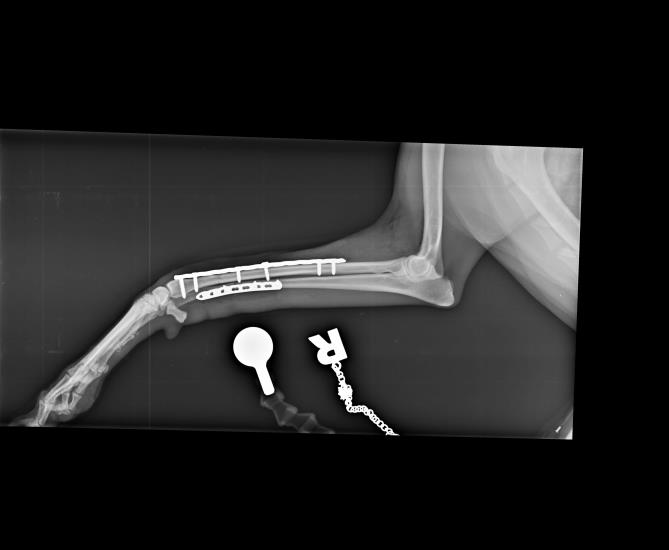

Often, only the radial fracture is stabilised, as this provides enough support for the ulna to heal by secondary bone healing. However, the blood supply to the distal radius and ulna is somewhat scarce due to the small amount of soft tissue surrounding the bone in Whippets and other small breeds. This can result in prolonged healing times. For this reason, plating of both bones was carried out. This gives maximum support and allows for the slow healing process to take place.

The radiograph below shows the repair with two locking compression plates.